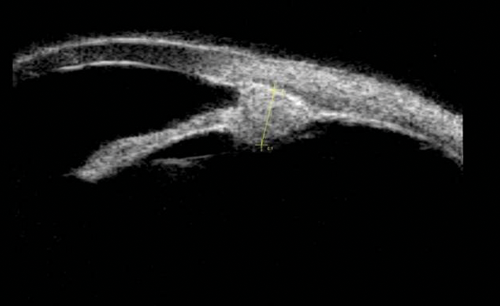

Figure 6a: Ciliary body melanoma.

Figure 6b: Melanoma obliterating the angle and extending posteriorly involving the pars plana.

Anterior segment cysts and tumours

The most common anterior segment tumours imaged in ophthalmology are iris tumours, these can be both pigmented and non-pigmented; irido-ciliary cysts; iris tumours that involve the ciliary body; and ciliary body tumours. In lightly pigmented irides, the iris pigment epithelium can be clearly imaged with UBM and anterior segment OCT (AS-OCT). AS-OCT is able to delineate the border of thicker-walled cysts but cannot penetrate the iris pigment epithelium. UBM therefore remains the best method of imaging and following up the majority of anterior segment tumours. Some examples include: ciliary body melanoma (Figure 6), ciliary body lesion (Figure 8) and iris hamartoma (Figure 9).